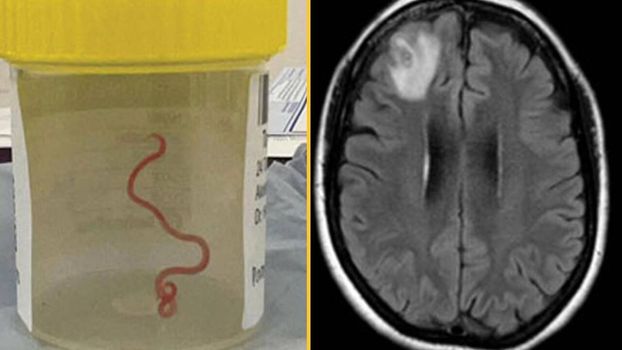

An MRI scan of the woman’s brain discovered a parasitic roundworm, or more specifically, a motile helminth.

The worm was living in the right frontal lobe section of her brain. Doctors then successfully removed the roundworm, which measured 8cm in length and 1mm in diameter.

Neurosurgeon Dr Hari Priya Bandi describes her “shock” at discovering an 8cm-long roundworm in the brain of a patient, adding that the parasite was still “wiggling” as she removed it.

Initially docs discovered the “string like structure” in her brain and then it began to move, much to their astonishment.